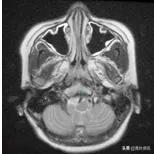

休息3个月后,症状完全消失,珊珊又回到了梦寐以求的学校里。多次复查发现珊珊的病情在逐渐好转,最近一次检查奇迹般的发现颈部软组织完全消失,破坏的骨质也基本修复(图二)。

图二 治疗后2年复查MRI

而且这一年来,珊珊又长高了不少,没有出现当初担心的放疗导致颈部发育畸形的问题。